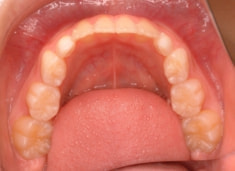

治療前

治療開始時